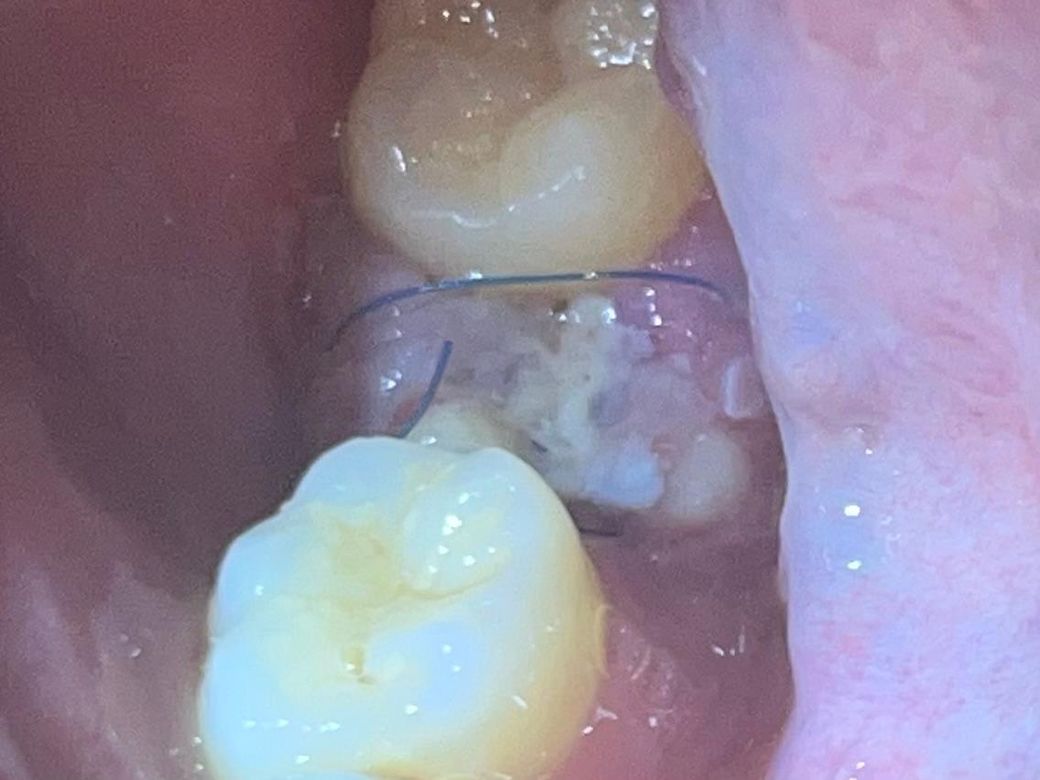

어금니 발치 혈병 관련 질문있습니다.

20260211(이틀전)에 뿌리만 남아있던 어금니를 발치했습니다. 발치 당시 선생님께서 굉장히 간단하게 뽑아서 통증이나 얼굴이 붓는 거는 거의 없을 것이라고 했습니다.

1. 왜 저의 혈병은 이렇게 거뭇거뭇한 것일까요? 드라이소켓 확률이 있나요? (아프거나 냄새가 나지는 않습니다.)

2. 그리고 이것이 혈병이 맞나요?

• 1번 째 사진

1. 그냥 이물질 낀겁니다

2. 혈병에서 치유를 위한 염증,육아조직으로 바뀌고 있는겁니다

1. 혈병의 경우에는 원래 약간 거뭇하게 보입니다.

2.초기에는 혈병이 나타나지만 시간이 지나면 섬유화가 진행되어 지금처럼 하얗게 보입니다.